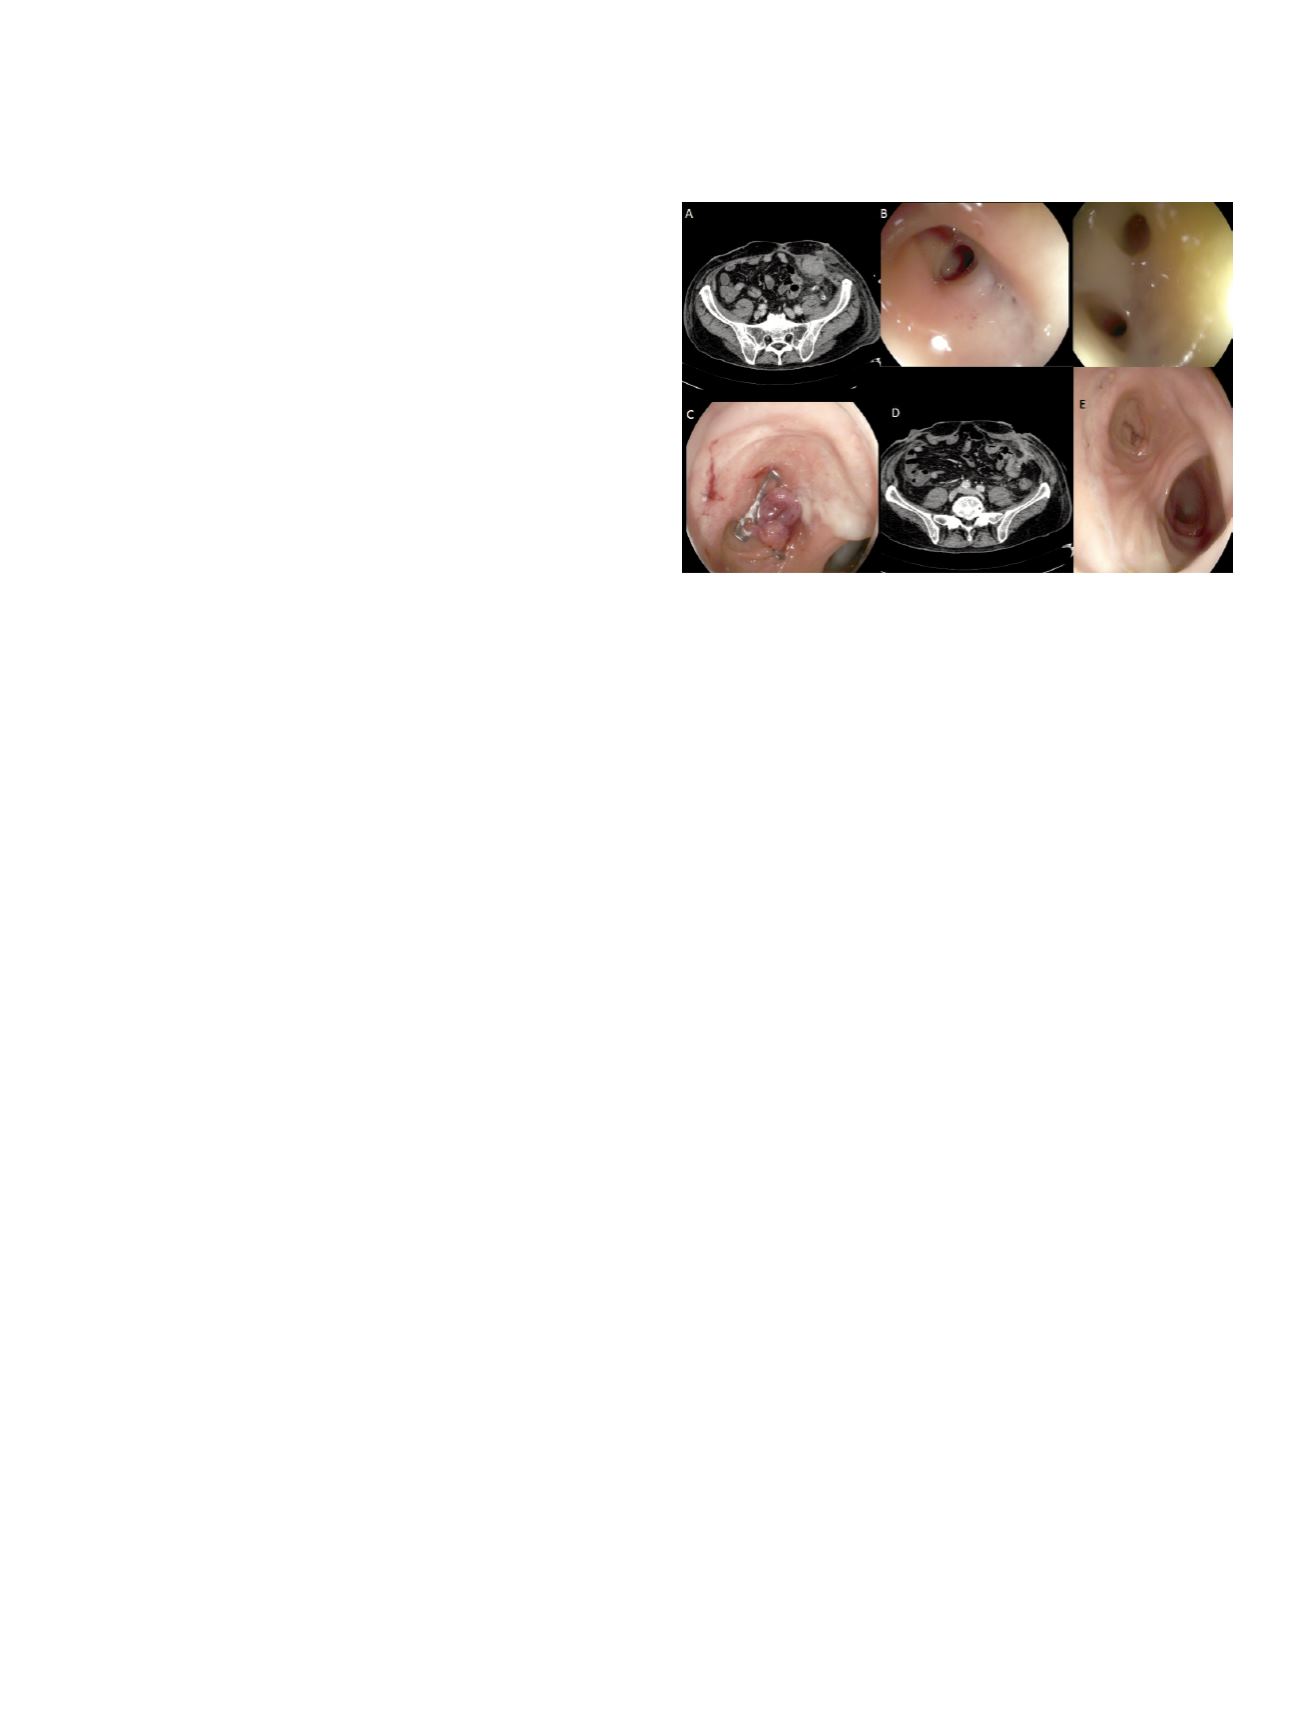

A 67-year-old man underwent left

hemicolectomy for sigmoid colon cancer. A colocolonic end-to-

side anastomosis was performed. Five months later the patient was

admitted to the intensive care unit because of worsening clinical

status. An anastomotic dehiscence was diagnosed by use of a CT scan

Fig 1 A). Air was also present in the retroperitoneum. Endoscopy was

immediately performed, and two areas of anastomotic dehiscence

of approximately 5 and 10 mm of colocutaneous fistula occurred

in the cul de sac (B). The cap was applied against the fistula, and

aspiration was performed to remove a large amount of collected

fluid and debris outside the colon. The anchor probe was intro-

duced through the fistula and the grasped tissue firmly pulled

inside the cap. Continuous suction was applied to assist traction of

the anchor probe. It was impossible to correctly deploy the OTSC

due to insufficient grasping and suction caused by fibrosis, scarred

and hardened postsurgical tissues at the edges of the lesion. Such, to

allows to capture a large amount of soft tissue above the leakage, we

positioning the device at medial tract of the cul de sac and without

using any grasper. Healthy mucosa were fully pulled and suctioned

into the cap, then the clip was deployed (C).

Results:

The patient was allowed to have a full diet 24 hours later,

after a Gastrografin enema confirmed sealing. The patient was

discharged from the hospital 1 week later. CT scan performed 1

month after hospital discharge confirmed that the leakage was

sealed (D). Endoscopy confirmed a new cul de sac, with healthy

mucosa without OTSC (E).